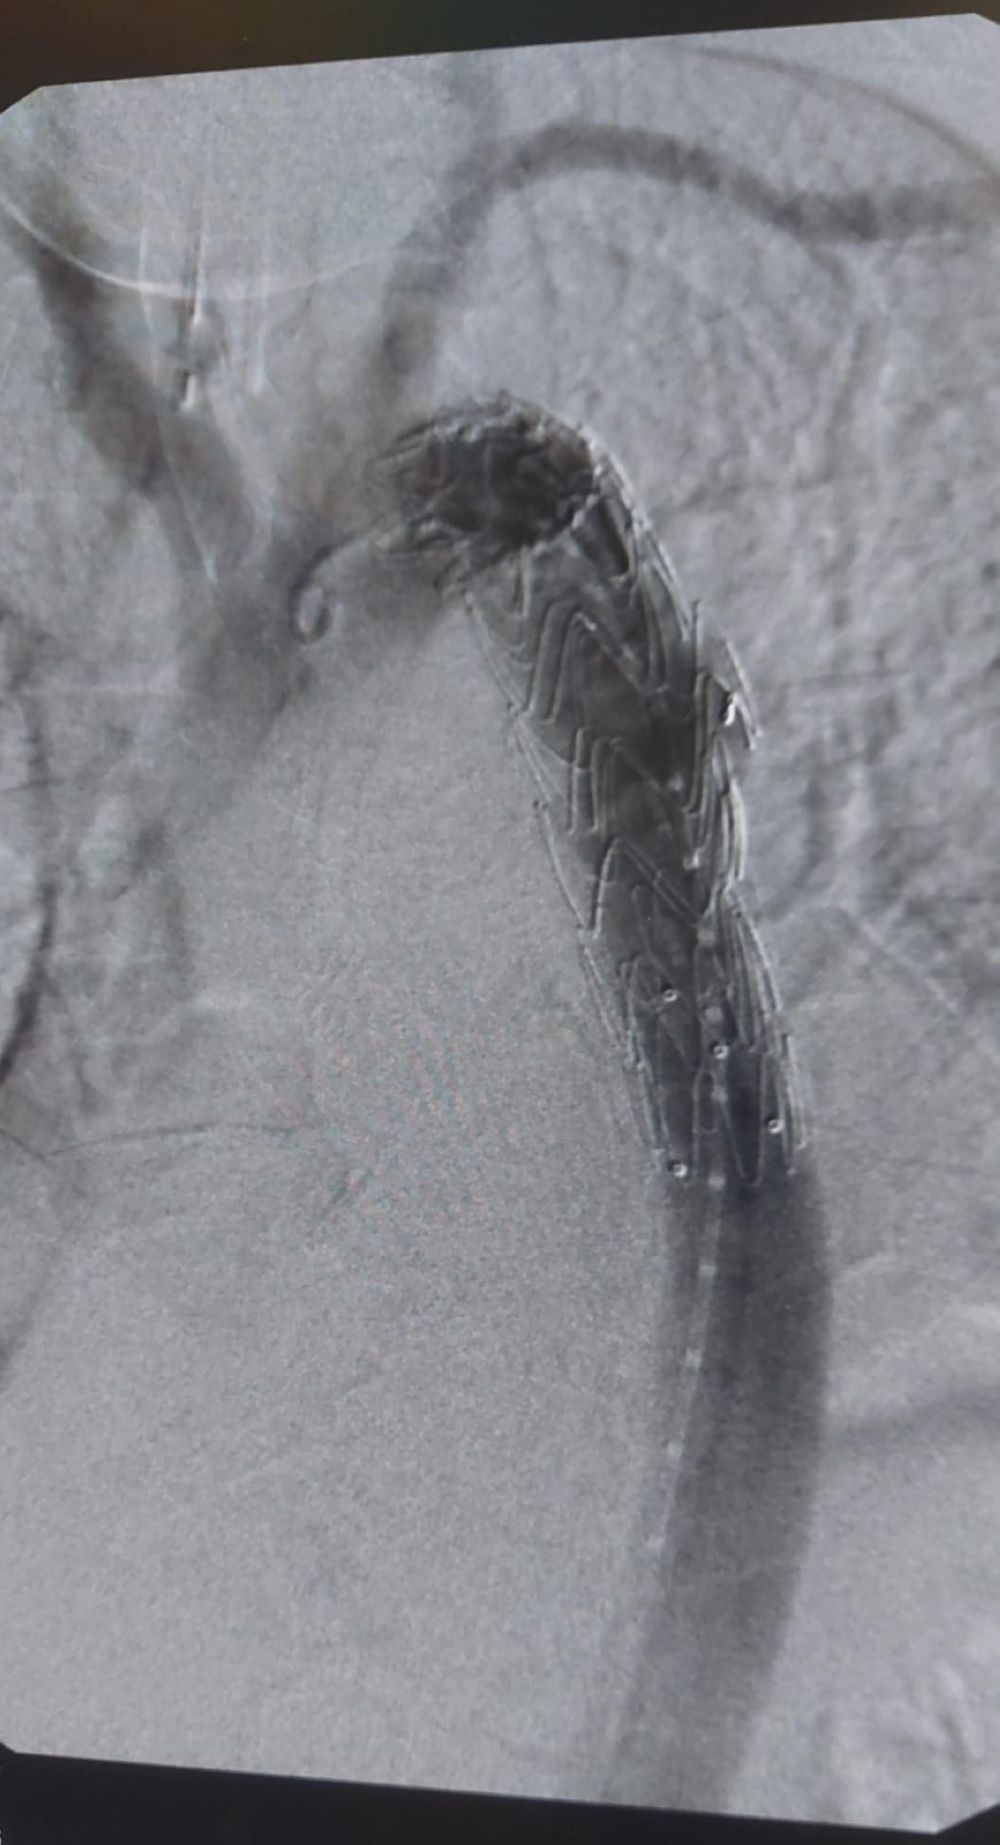

وقال التجمع "إن الفريق الطبي المعالج للحالة في قسم جراحة الأوعية الدموية بالمستشفى باشر على الفور بتنويم المريض والتحكم في ضغط الدم وعمل التحاليل والاستشارات اللازمة وتحضير المريض لتركيب دعامة مغطاة بالشريان الأورطي عن طريق قسطرة الأوعية التداخلية تحت تأثير التخدير الكلي، حيث تم تركيب الدعامات المغطاة بفضل الله بنجاح دون تسجيل أي مضاعفات خلال عملية استغرقت حوالي الساعتين".